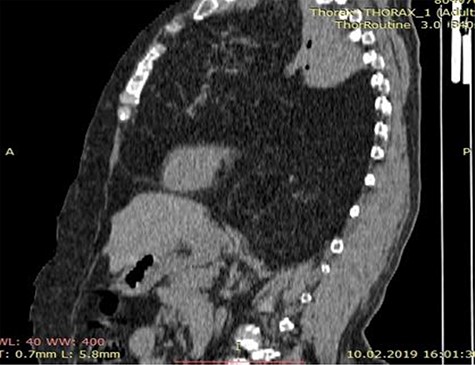

CT scan of the chest showing a large anterior mediastinum mass projecting to the right and left hemithorax with wide range of fat tissue density.